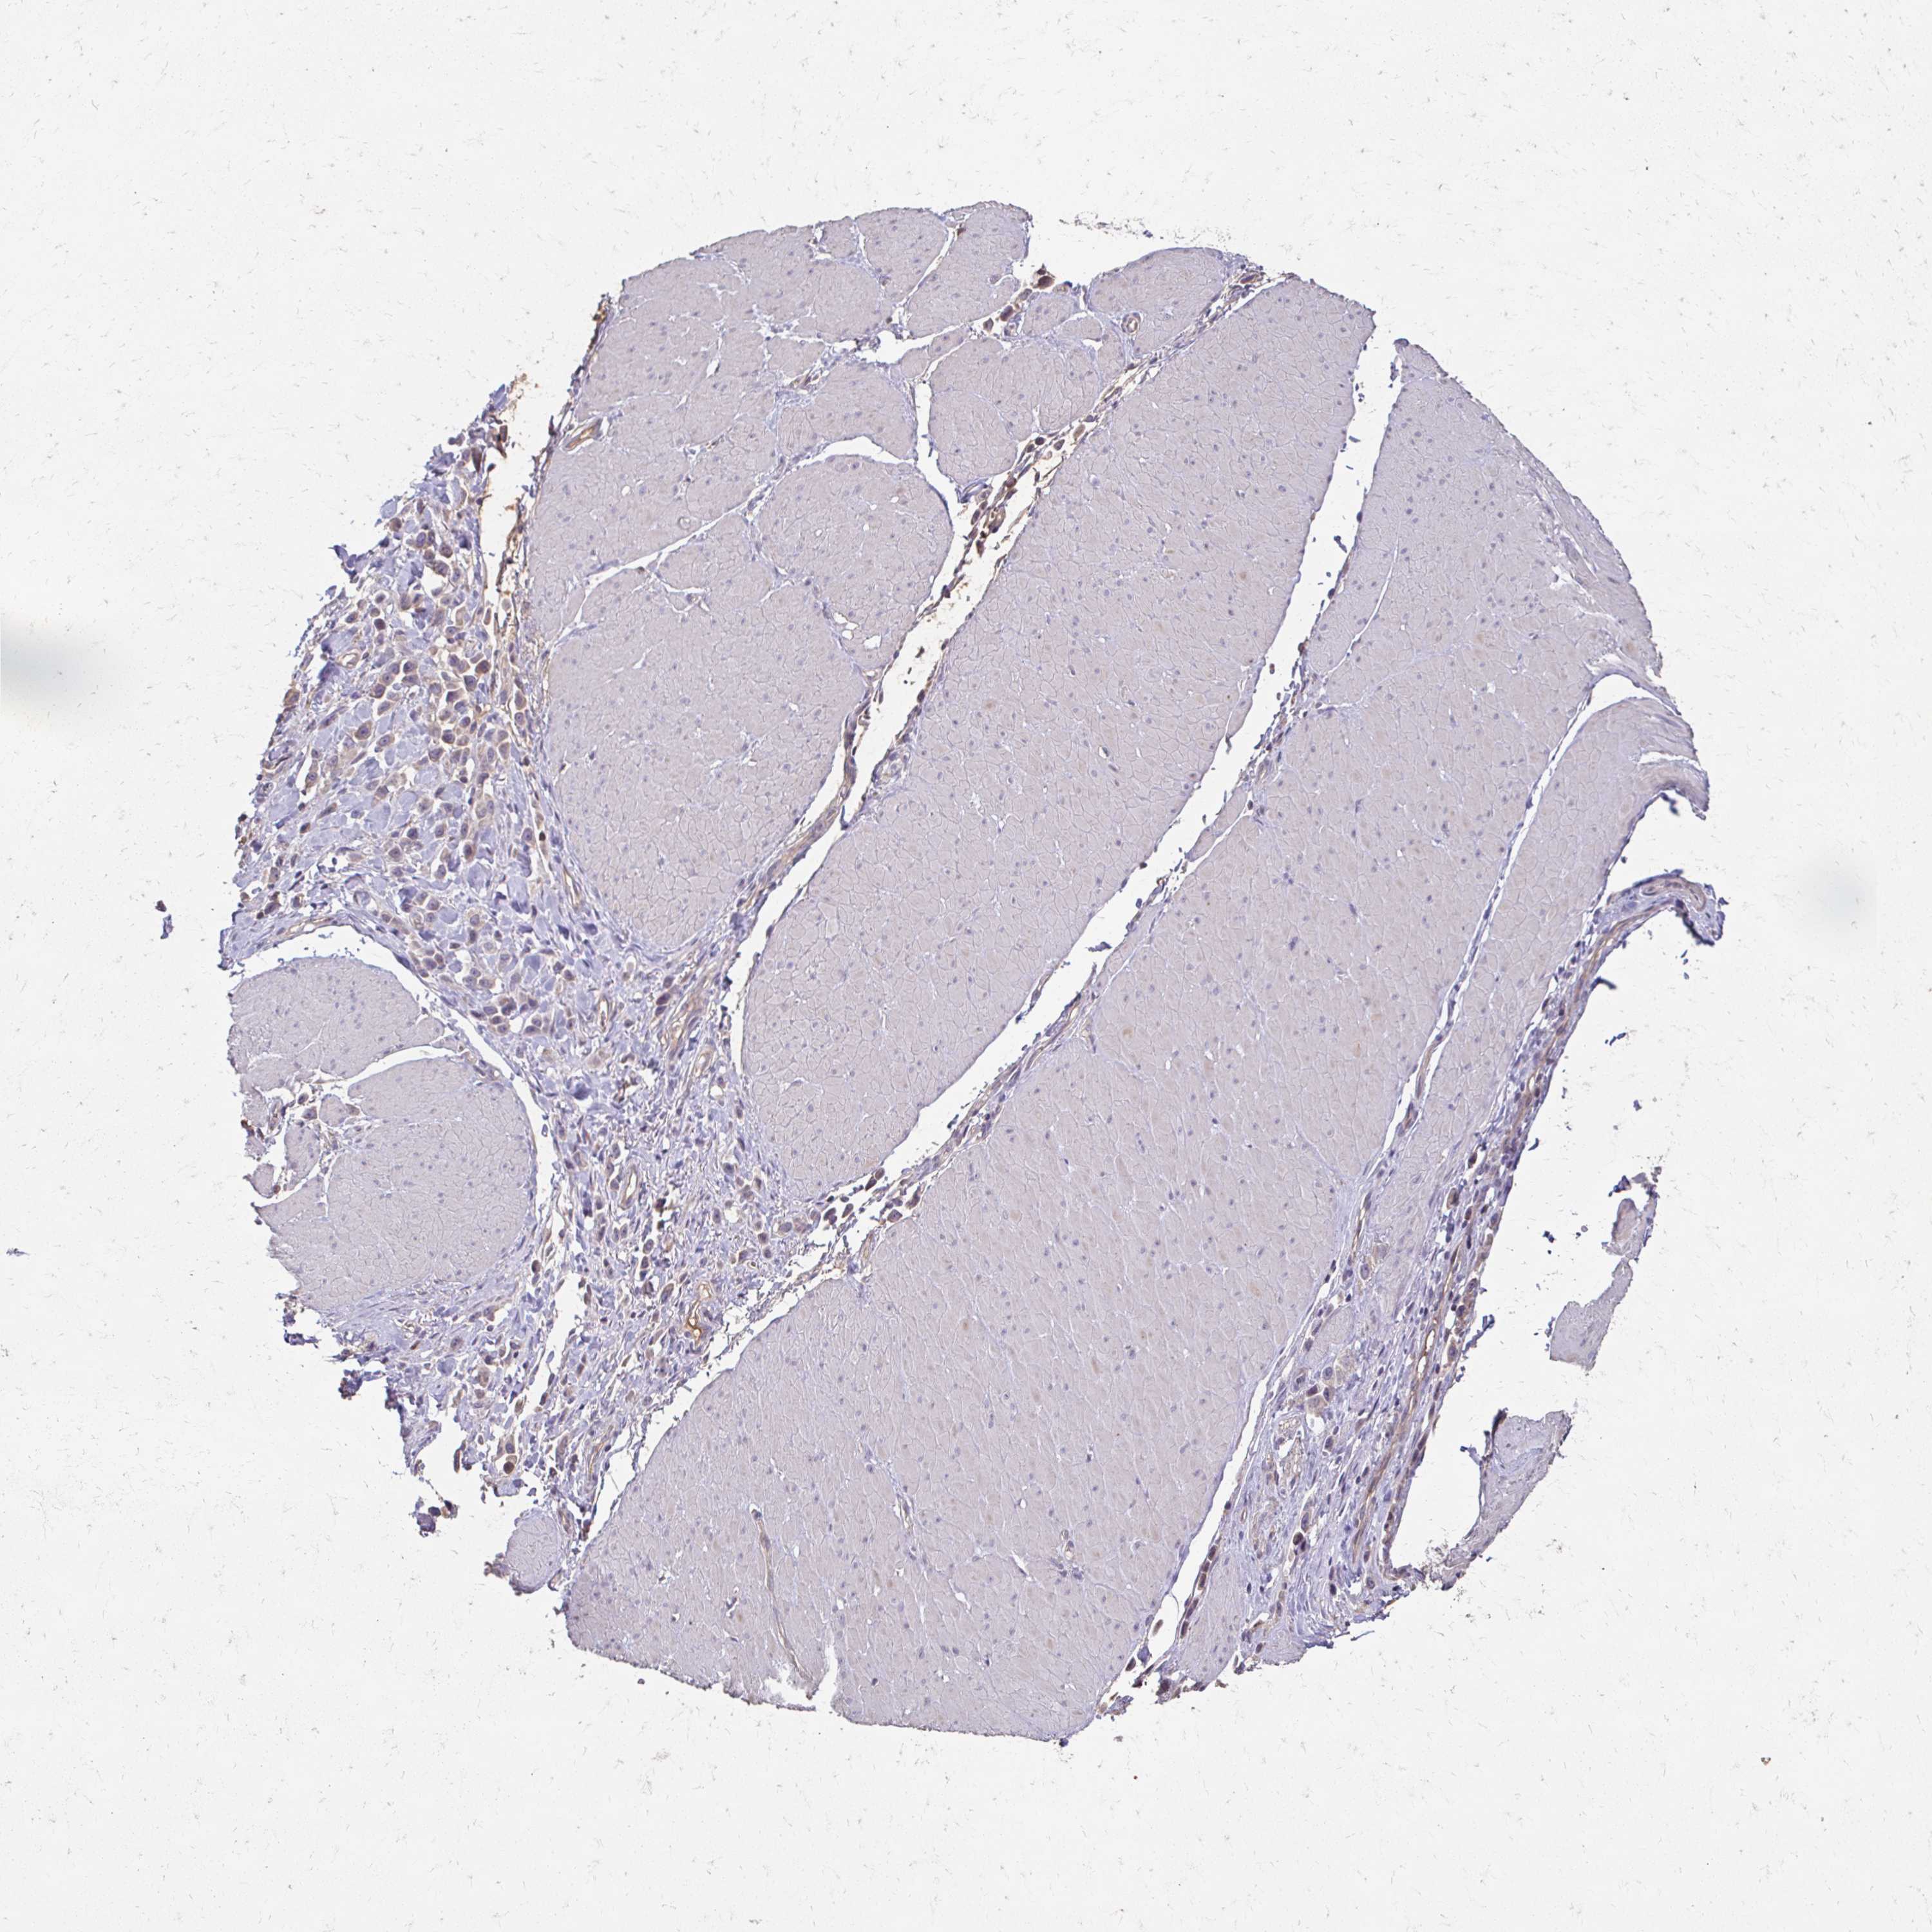

STOMACH CANCER - Protein expressioni

A mouse-over function shows sample information and annotation data. Click on an image to view it in a full screen mode. Samples can be filtered based on level of antibody staining by selecting one or several of the following categories: high, medium, low and not detected. The assay and annotation is described here.

Note that samples used for immunohistochemistry by the Human Protein Atlas do not correspond to samples in the TCGA dataset.

Antibody stainingi

Antibody staining in the annotated cell types in the current human tissue is reported as not detected, low, medium, or high, based on conventional immunohistochemistry profiling in selected tissues. This score is based on the combination of the staining intensity and fraction of stained cells.

Each image is clickable and will lead to virtual microscopy that enables deeper exploration of all samples and also displays staining intensity scores, fraction scores and subcellular localization as well as patient and tissue information for each sample.

Antibody HPA041061

Staining

High

Medium

Low

Not detected

Intensity

Strong

Moderate

Weak

Negative

Quantity

>75%

75%-25%

<25%

None

Location

Nuclear

Cytoplasmic/membranous

Cytoplasmic/membranous,nuclear

Adenocarcinoma, NOS